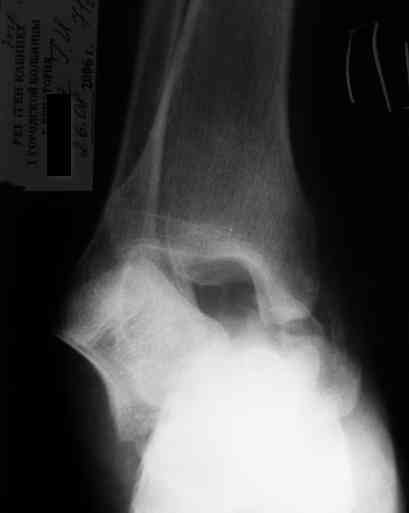

Уважаемый Александр! Как обещал представляю Р-граммы и операционные фото.

Последний снимок

Мнение по поводу тарана? АН есть?

> Мнение по поводу тарана? АН есть?

Типичная картина некроза.

На мой взгляд, у больного асептический некроз таранной кости, осложненный гнойным артритом голеностопного сустава (по снимку не понятно, что это - фистулография или простая рентгенограмма). Оптимален артродез голеностопного сустава, объем резекции таранной кости определится только интраоперационно. Большая проблема - метод фиксации. Работая, в основном, с пациентами пожилого и старческого возраста могу сказать, что ЧКОС они переносят плохо. Адекватный уход за аппаратом возможен только в условиях стационара. Возможность самостоятельной работы с аппаратом, например для ликвидации укорочения, крайне сомнительна. Кроме того, укорочение 3 см (до 5 см) у данной категории больных легче компенсировать ортопедической обувью. К сожалению и фиксирующие повязки (гипсовые и различные "касты")- не лучший вариант для пожилых людей (пролежни и флектены просто на "ровном месте"). В данном случае я бы применил простую "фиксирующею" компоновку аппарата Илизарова, с возможностью "отступления" к голеностопному брэйсу (тутору). Основная задача - максимальное восстановление самообслуживания больного и, по возможности, избежать "этапных" операций.